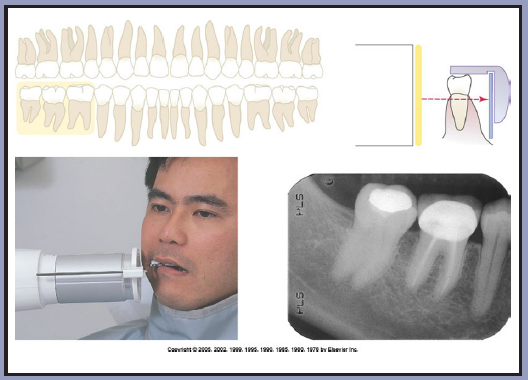

Procedure for the Maxillary Molar Region

1. Assemble the posterior receptor holding device and insert the receptor horizontally in the posterior biteblock. Use a type 2 receptor.

2. Center the receptor on the molars. (Figure 23) The receptor should be parallel with the long axis of the tooth. (Figure 24) Position the receptor in the palate so that the entire tooth length will appear on the radiograph with approximately a one-eighth inch border below the cuspal ridge. Align the anterior border of the receptor with the second premolar so that the image captured on the anterior edge of the receptor will be the distal third of the second premolar. Position the biteblock on the occlusal surfaces of the teeth to be radiographed. Proper positioning in this step will place the central ray of the x-ray beam between the molars.

3. A cotton roll may be inserted between the mandibular teeth and the biteblock for patient comfort. Ask the patient to slowly but firmly bite onto the block to maintain the correct position.

4. Slide the aiming ring down the indicator rod; it should be as close to the skin as possible without actually touching the patient. Align the tube head close to the aiming ring, and center. (Figure 25)

5. Follow the receptor and equipment manufacturer's recommendation concerning exposure factors. Make the exposure.

6. This procedure should be followed for the opposite side molars.

Figure 23 – Maxillary Molars

Figure 23

Figure 24 – Maxillary Molars

Figure 24

Figure 25 – Maxillary Molars

Figure 25